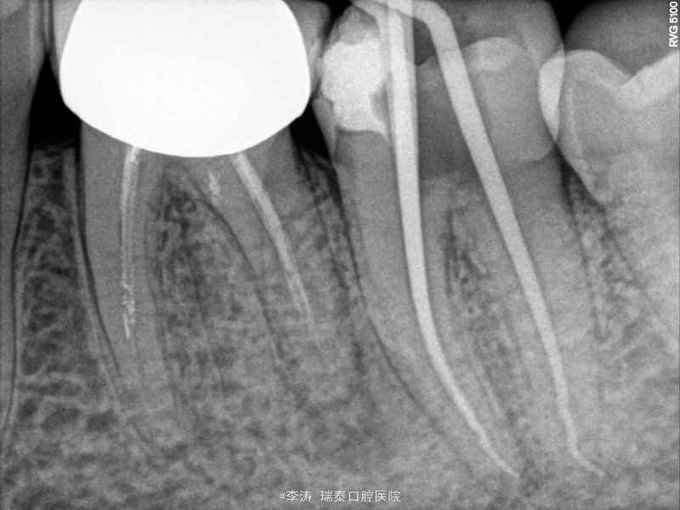

37牙去龋未净时穿髓 行根管治疗,开髓,根管预备,但根管预备封药后两天开始疼痛,叩痛明显,去除封药,未见明显分泌物,根管荡洗干燥后重新封药,但症状一直持续,自服止疼药后缓解,两周以后疼痛消失予以根充

根管封药后疼痛的原因?药物导致的根尖周炎?合创伤?预备时器械超出根尖孔导致的组织损伤?细菌感染? 怎样才能做到每次就诊封药后不疼?这真是一个值得考虑的问题